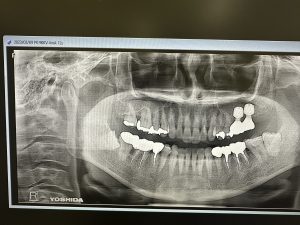

根管治療MTA.ヤグレーザー、ソケットリフトインプラント2本、ジルコニア9本

根尖から遠方より段々と骨化している

大きな病巣は5年位経過を追うと良い